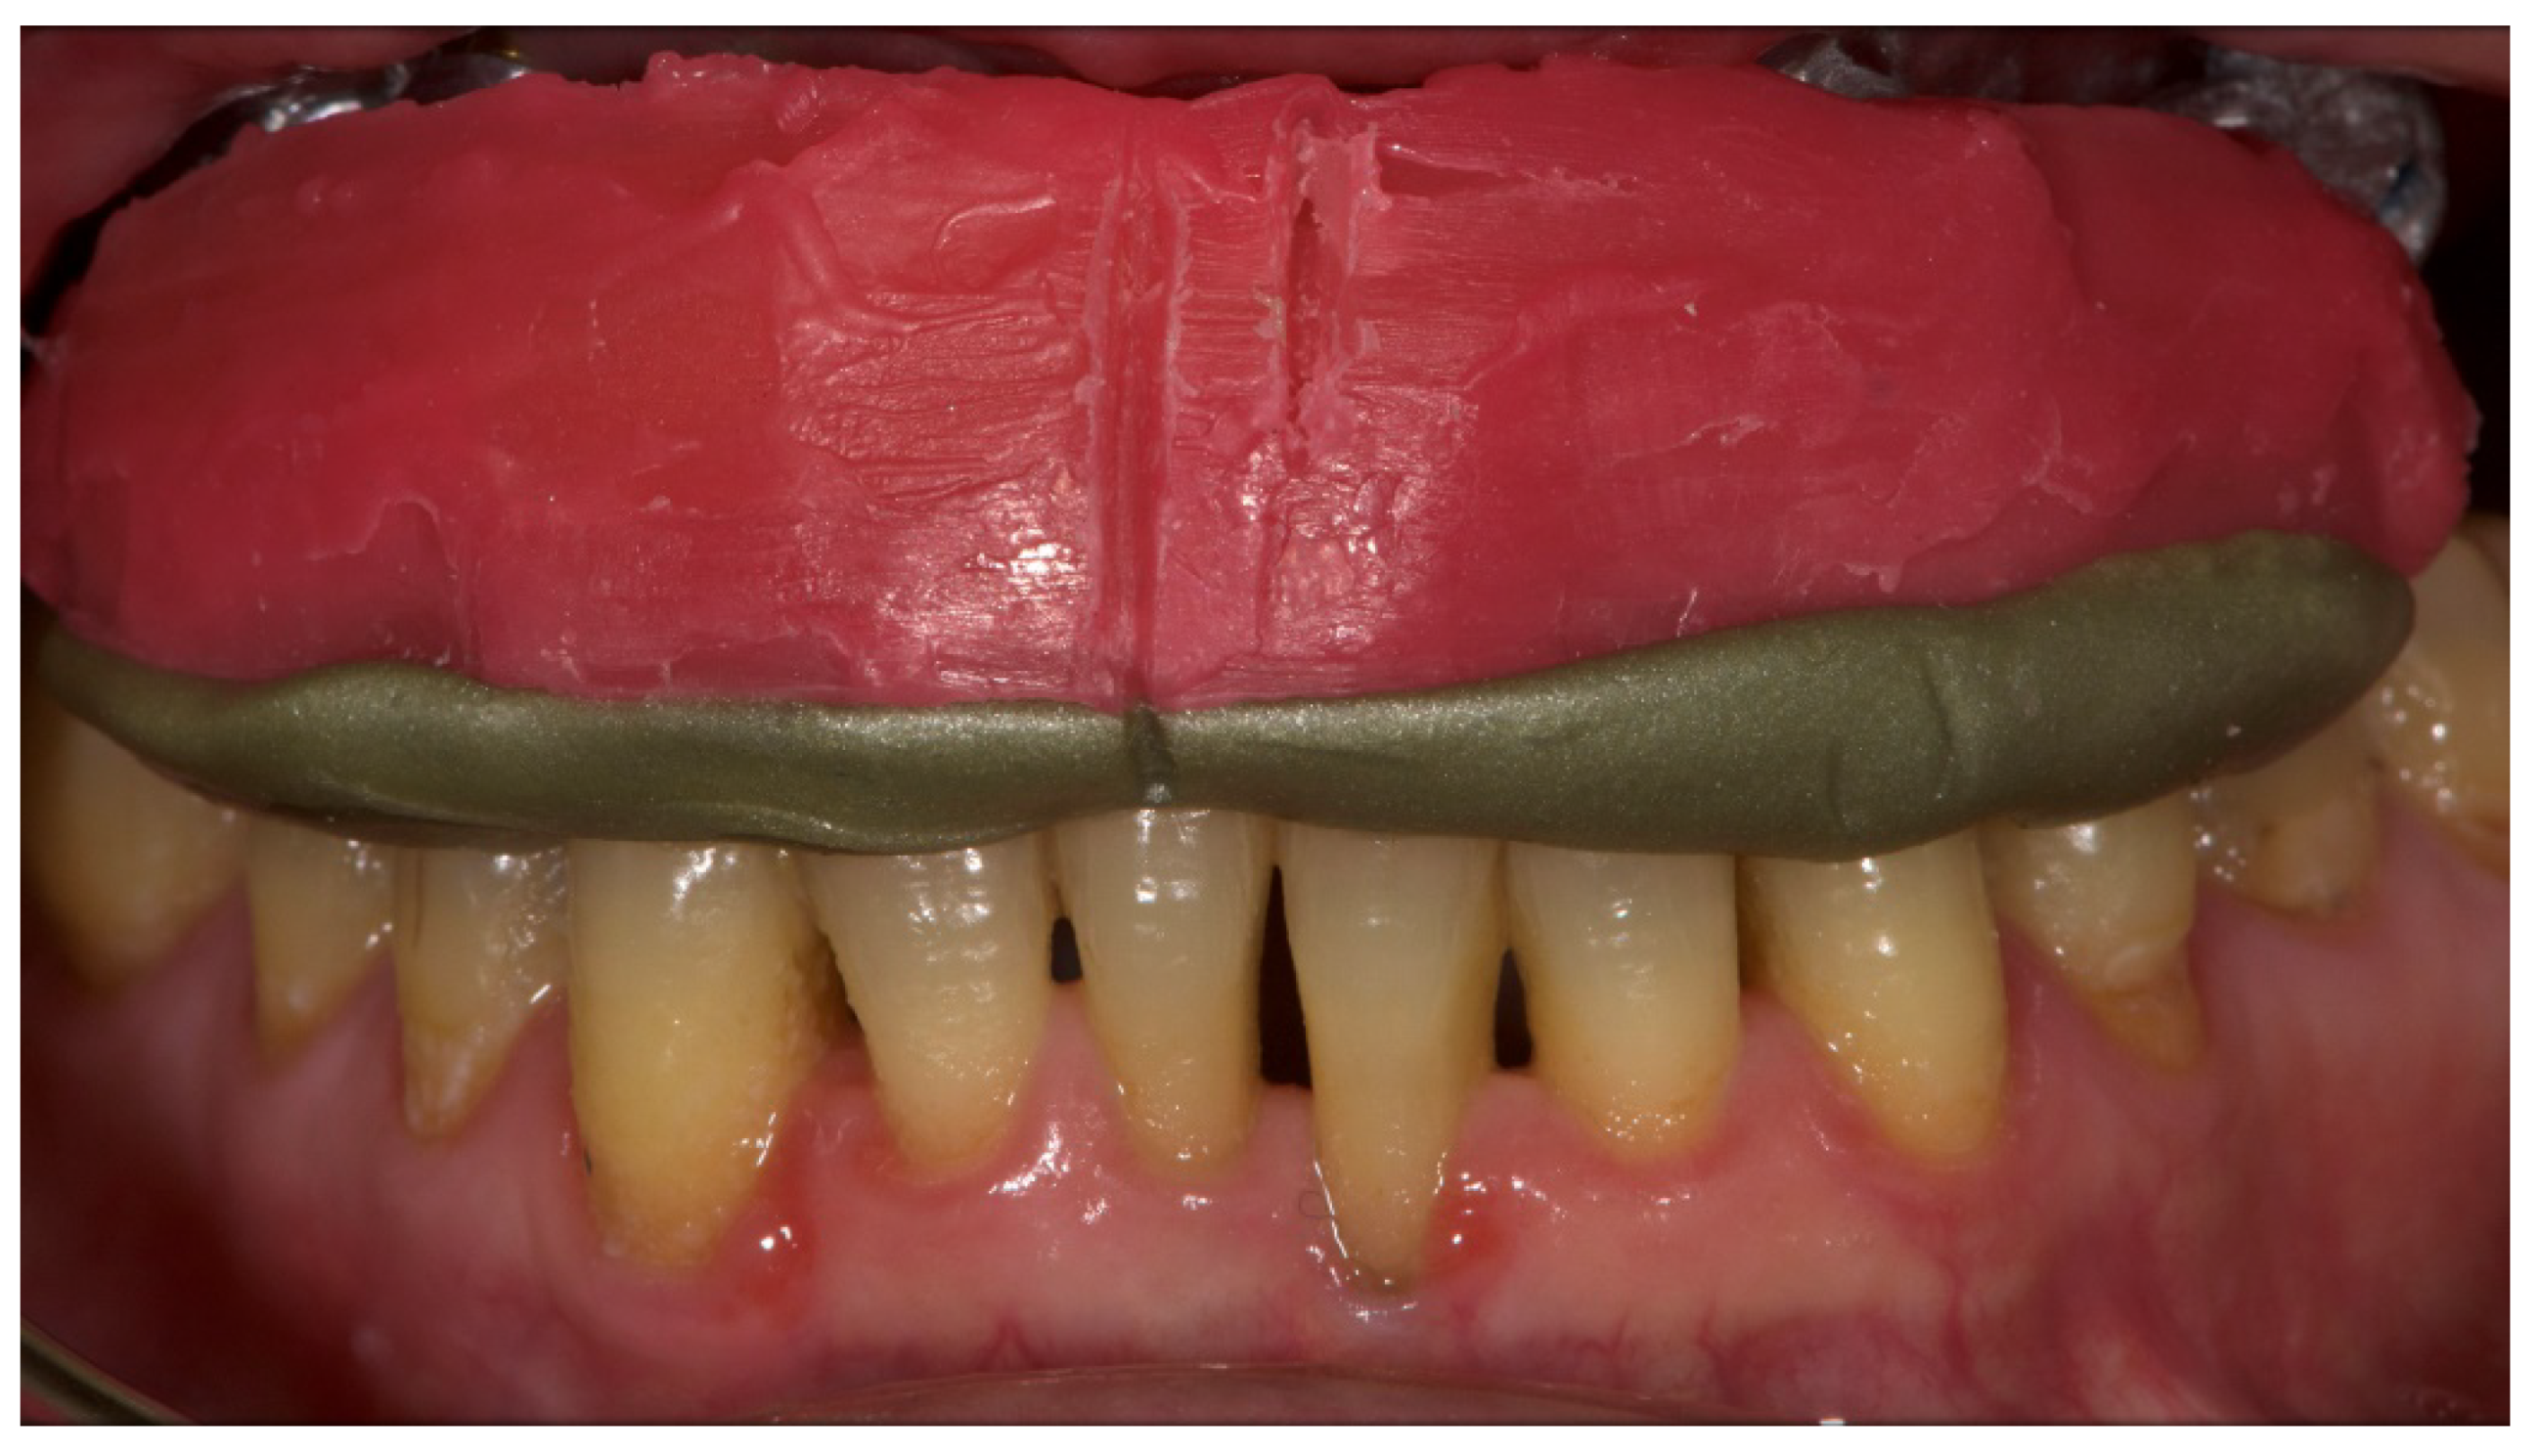

A partially edentulous 78-year-old woman with a complete screw-retained implant-support hybrid prosthesis (Figure 1) in the upper jaw and natural dentition in the lower jaw was referred to a private center in Rome, Italy, due to several continuous breakages of the prosthetic part of the implant-supported rehabilitation. After a preliminary interview, the patient stated that the implant treatment was finished two years before, but she had never been comfortable with this prosthesis (Figure 2). Relevant symptoms were phonetic difficulties, inability to maintain hygiene, and repeated breakages, leading to functional and esthetic issues (Figure 3). After that, the patient’s medical history was collected, and preoperative photographs, radiographs, periodontal screening results, and model casts were obtained for initial evaluation (Figure 4). During the clinical examination, the actual prosthesis was unscrewed, due to teeth detachments, and replaced with the old temporary prosthesis delivered by the patient. Both existing prostheses were evaluated and judged inaccurate, with particular attention to the fit of the prosthesis, the vertical dimension of occlusion, phonetics, facial support, and lip position. All the possible treatment options were then discussed and evaluated together with the patient. The main concerns of maintaining the previously placed implants were some exposed threads and the troubling disparallelism that makes the prosthetic treatment difficult, increasing the risk for biological complications and technical complications, respectively (Figure 5). Nevertheless, the patient refused a complete removable denture, so that implant removal would lead to placement of new implants, in combination with guided bone reconstruction and soft tissue management. This treatment plan may have the risks of implant failure and increased patient morbidity (Table 1 and Table 2). An implant-supported fixed dental prosthesis was initially excluded due to the implant’s disparallelism. Hence, a maxillary implant-supported overdenture was initially considered quite possibly the best therapeutic option.

Figure 1.

Picture of the patient’s work and initial situation.

Figure 3.

The internal part of the prosthetic restoration, the one in contact with the mucosa, shows the incorrect shape of the pink flange, which leads to the accumulation of plaque and food.